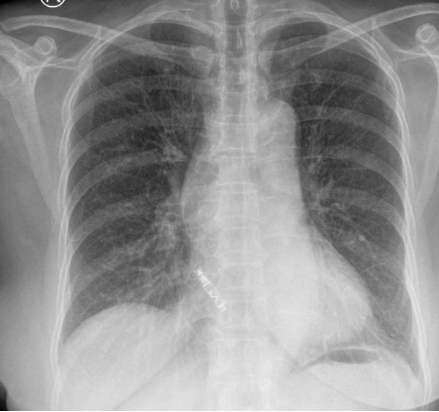

无导线起搏器体积仅胶囊大小(约 1.0cc),重量不足 2 克,通过导管直接植入心腔,无需切开皮肤或植入传统的电极导线,刚好解决了解剖变异问题。术中使用 Aveir AR 专用输送系统经右侧股静脉-下腔静脉血管途径顺利将起搏器送入右心房,并精准释放于右心耳,测试参数满意,术后心电监测记录到患者再次出现心脏停搏,起搏器及时启动帮助跳动,患者未发生不适症状。术后 24 小时程控起搏器阈值良好,工作状态无异常。患者头晕、心慌症状显著缓解,无需换药拆线,第三日即办理出院,如此效率,让患者及家属连连称赞。

心房无导线起搏器的出现,填补了无导线起搏技术在心房领域的空白,是心脏起搏技术发展的又一里程碑。它为复杂心脏病患者带来了更微创、更生理、更安全的治疗方案。而此次手术的成功,也标志着我院在复杂心脏介入治疗领域再上新台阶。」目前,患者已康复出院。